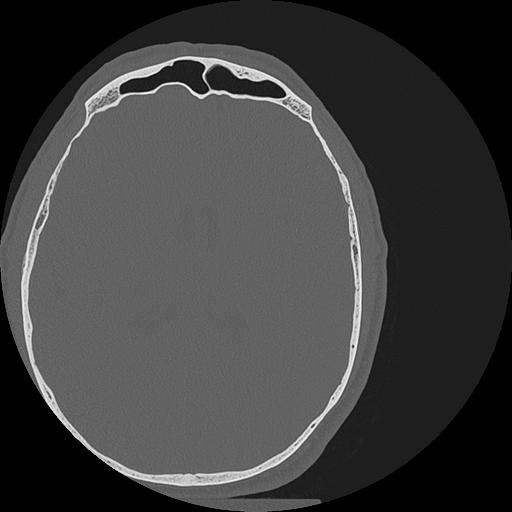

7 HUESO,,Vol,0.5,HUESO,,